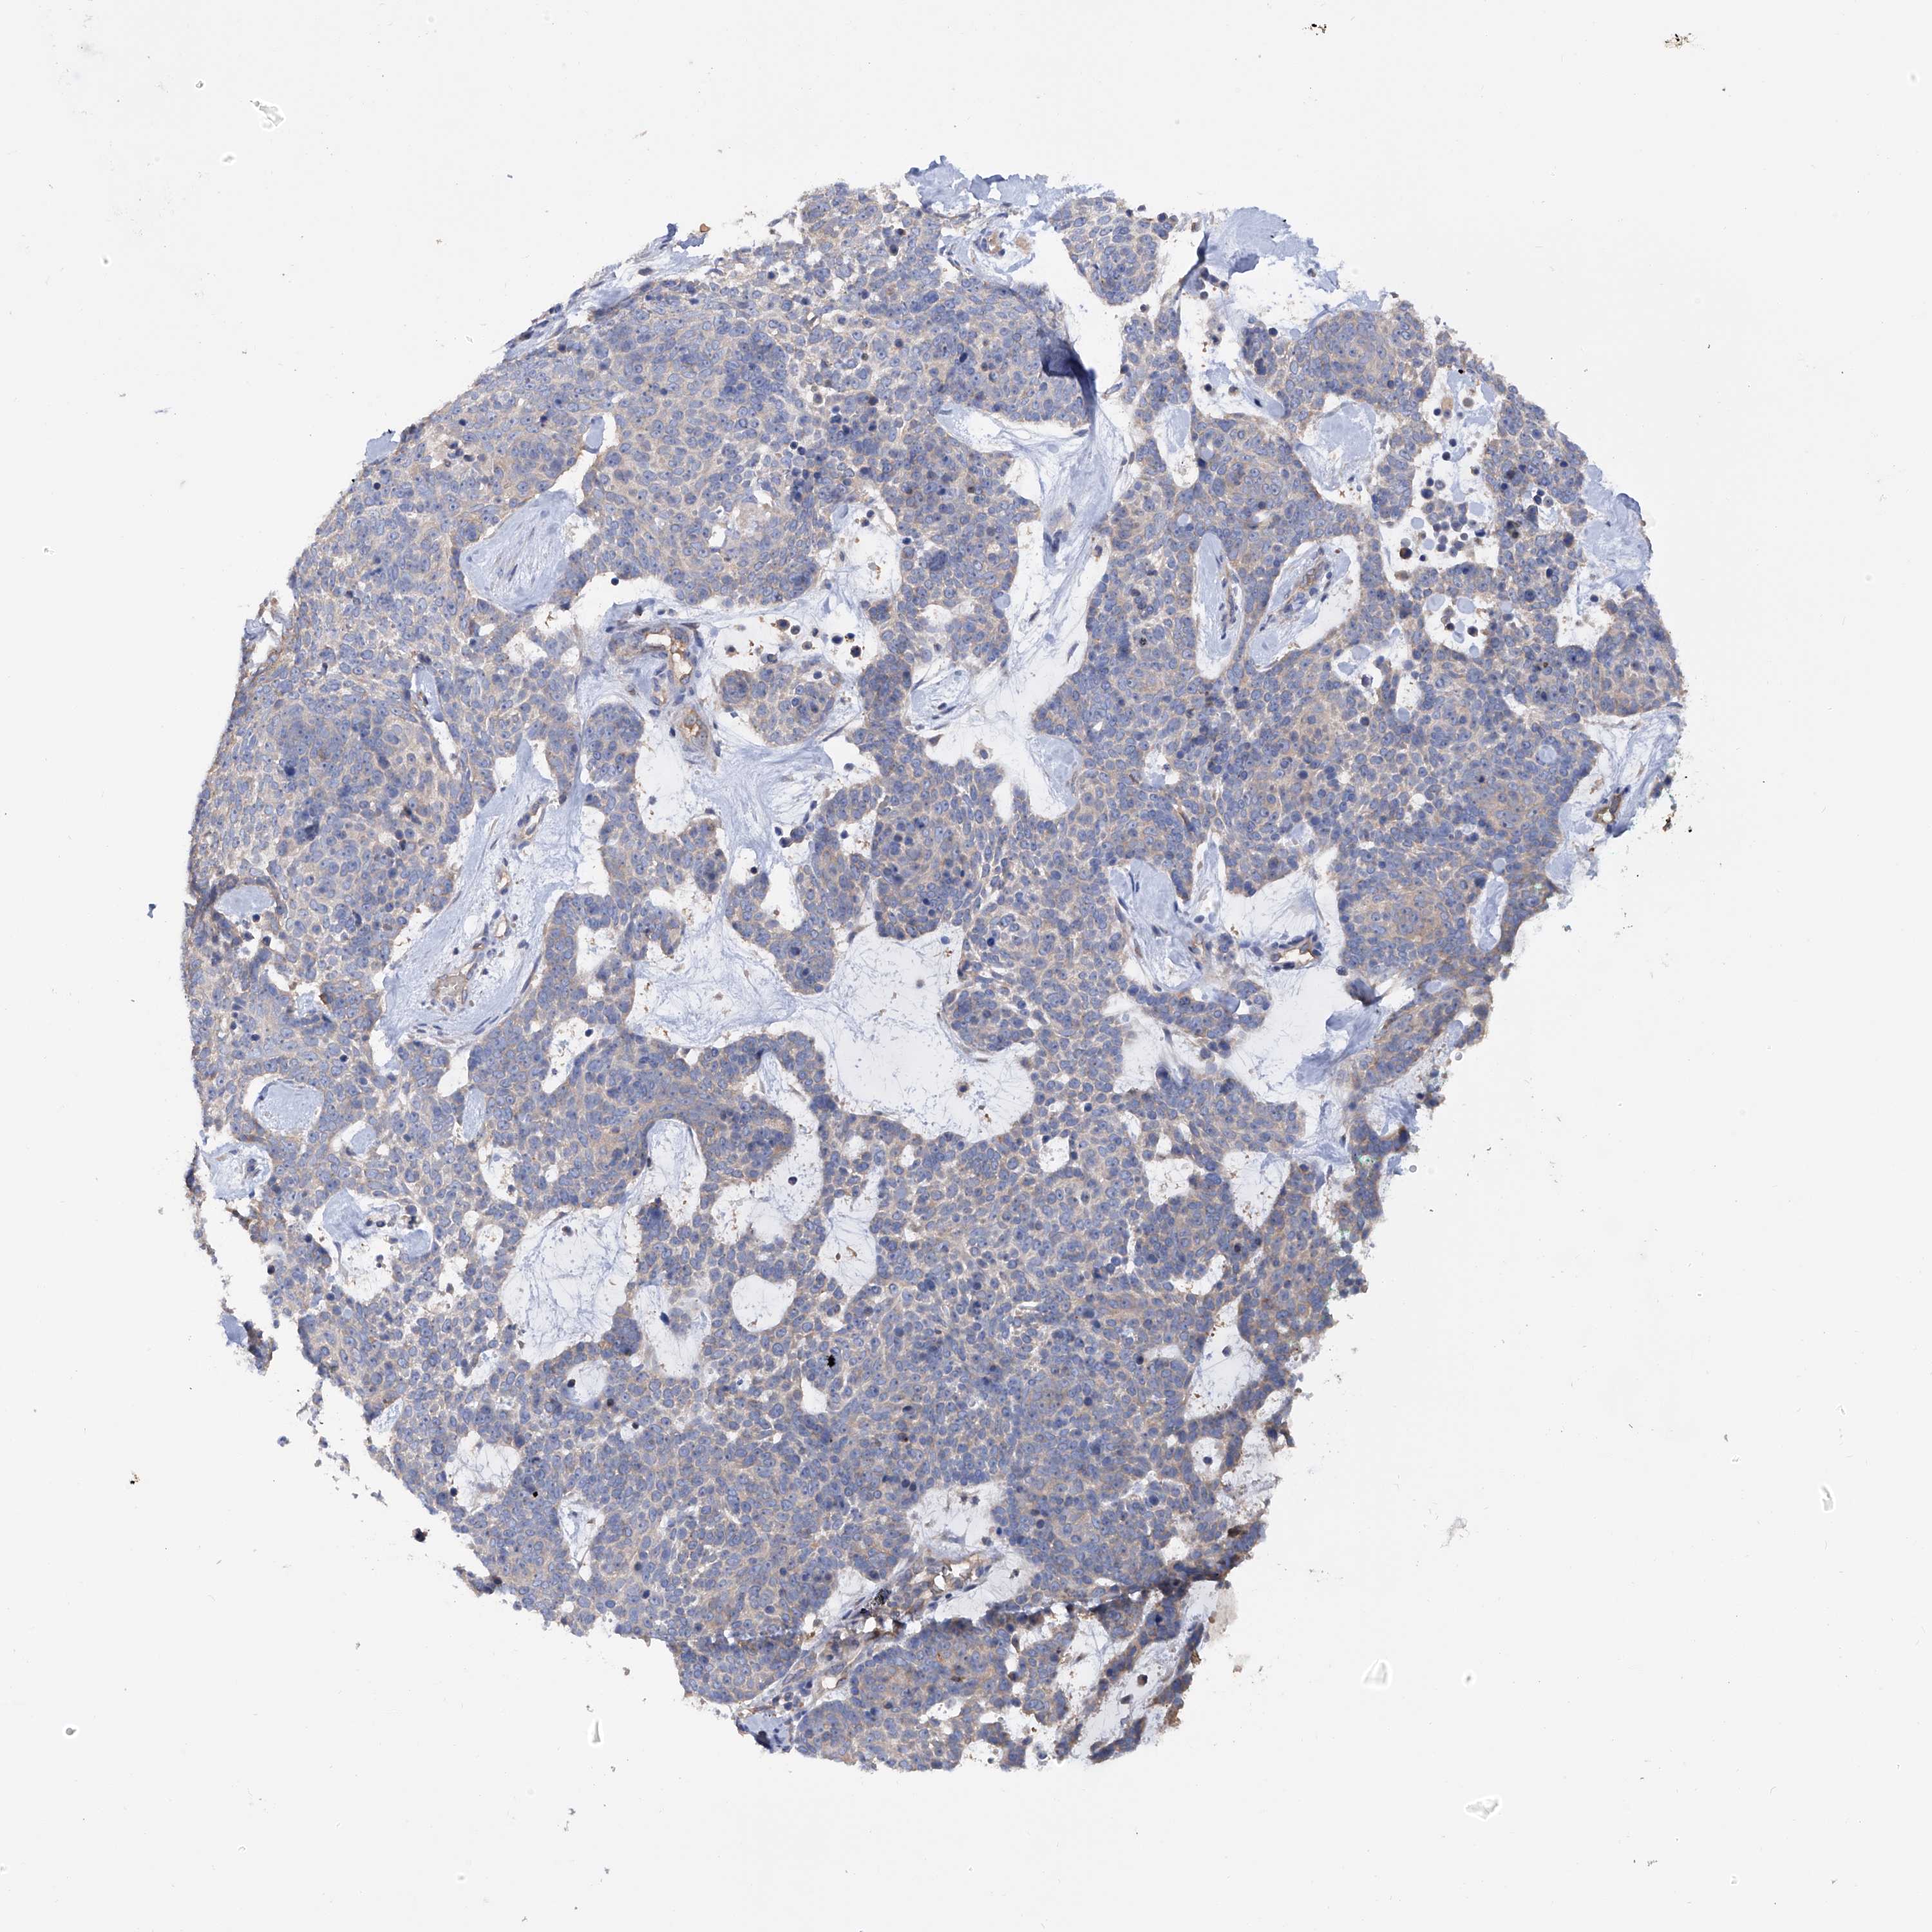

Basal cell and squamous cell cancer

SKIN CANCER - Protein expressioni

A mouse-over function shows sample information and annotation data. Click on an image to view it in a full screen mode. Samples can be filtered based on level of antibody staining by selecting one or several of the following categories: high, medium, low and not detected. The assay and annotation is described here.

Each image is clickable and will lead to virtual microscopy that enables deeper exploration of all samples and also displays staining intensity scores, fraction scores and subcellular localization as well as patient and tissue information for each sample.

Antibody HPA030145

Staining

Low

Weak

<25%

Location

Cytoplasmic/membranous,nuclear

Squamous cell carcinoma, metastatic, NOS